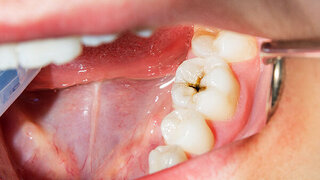

Zahl des Monats3,5 Milliarden Rund 3,5 Milliarden Menschen leiden unter Zahn- und Munderkrankungen, zeigt der „Global oral health status report” der Weltgesundheitsorganisation (WHO). 26.12.2022 Gesellschaft